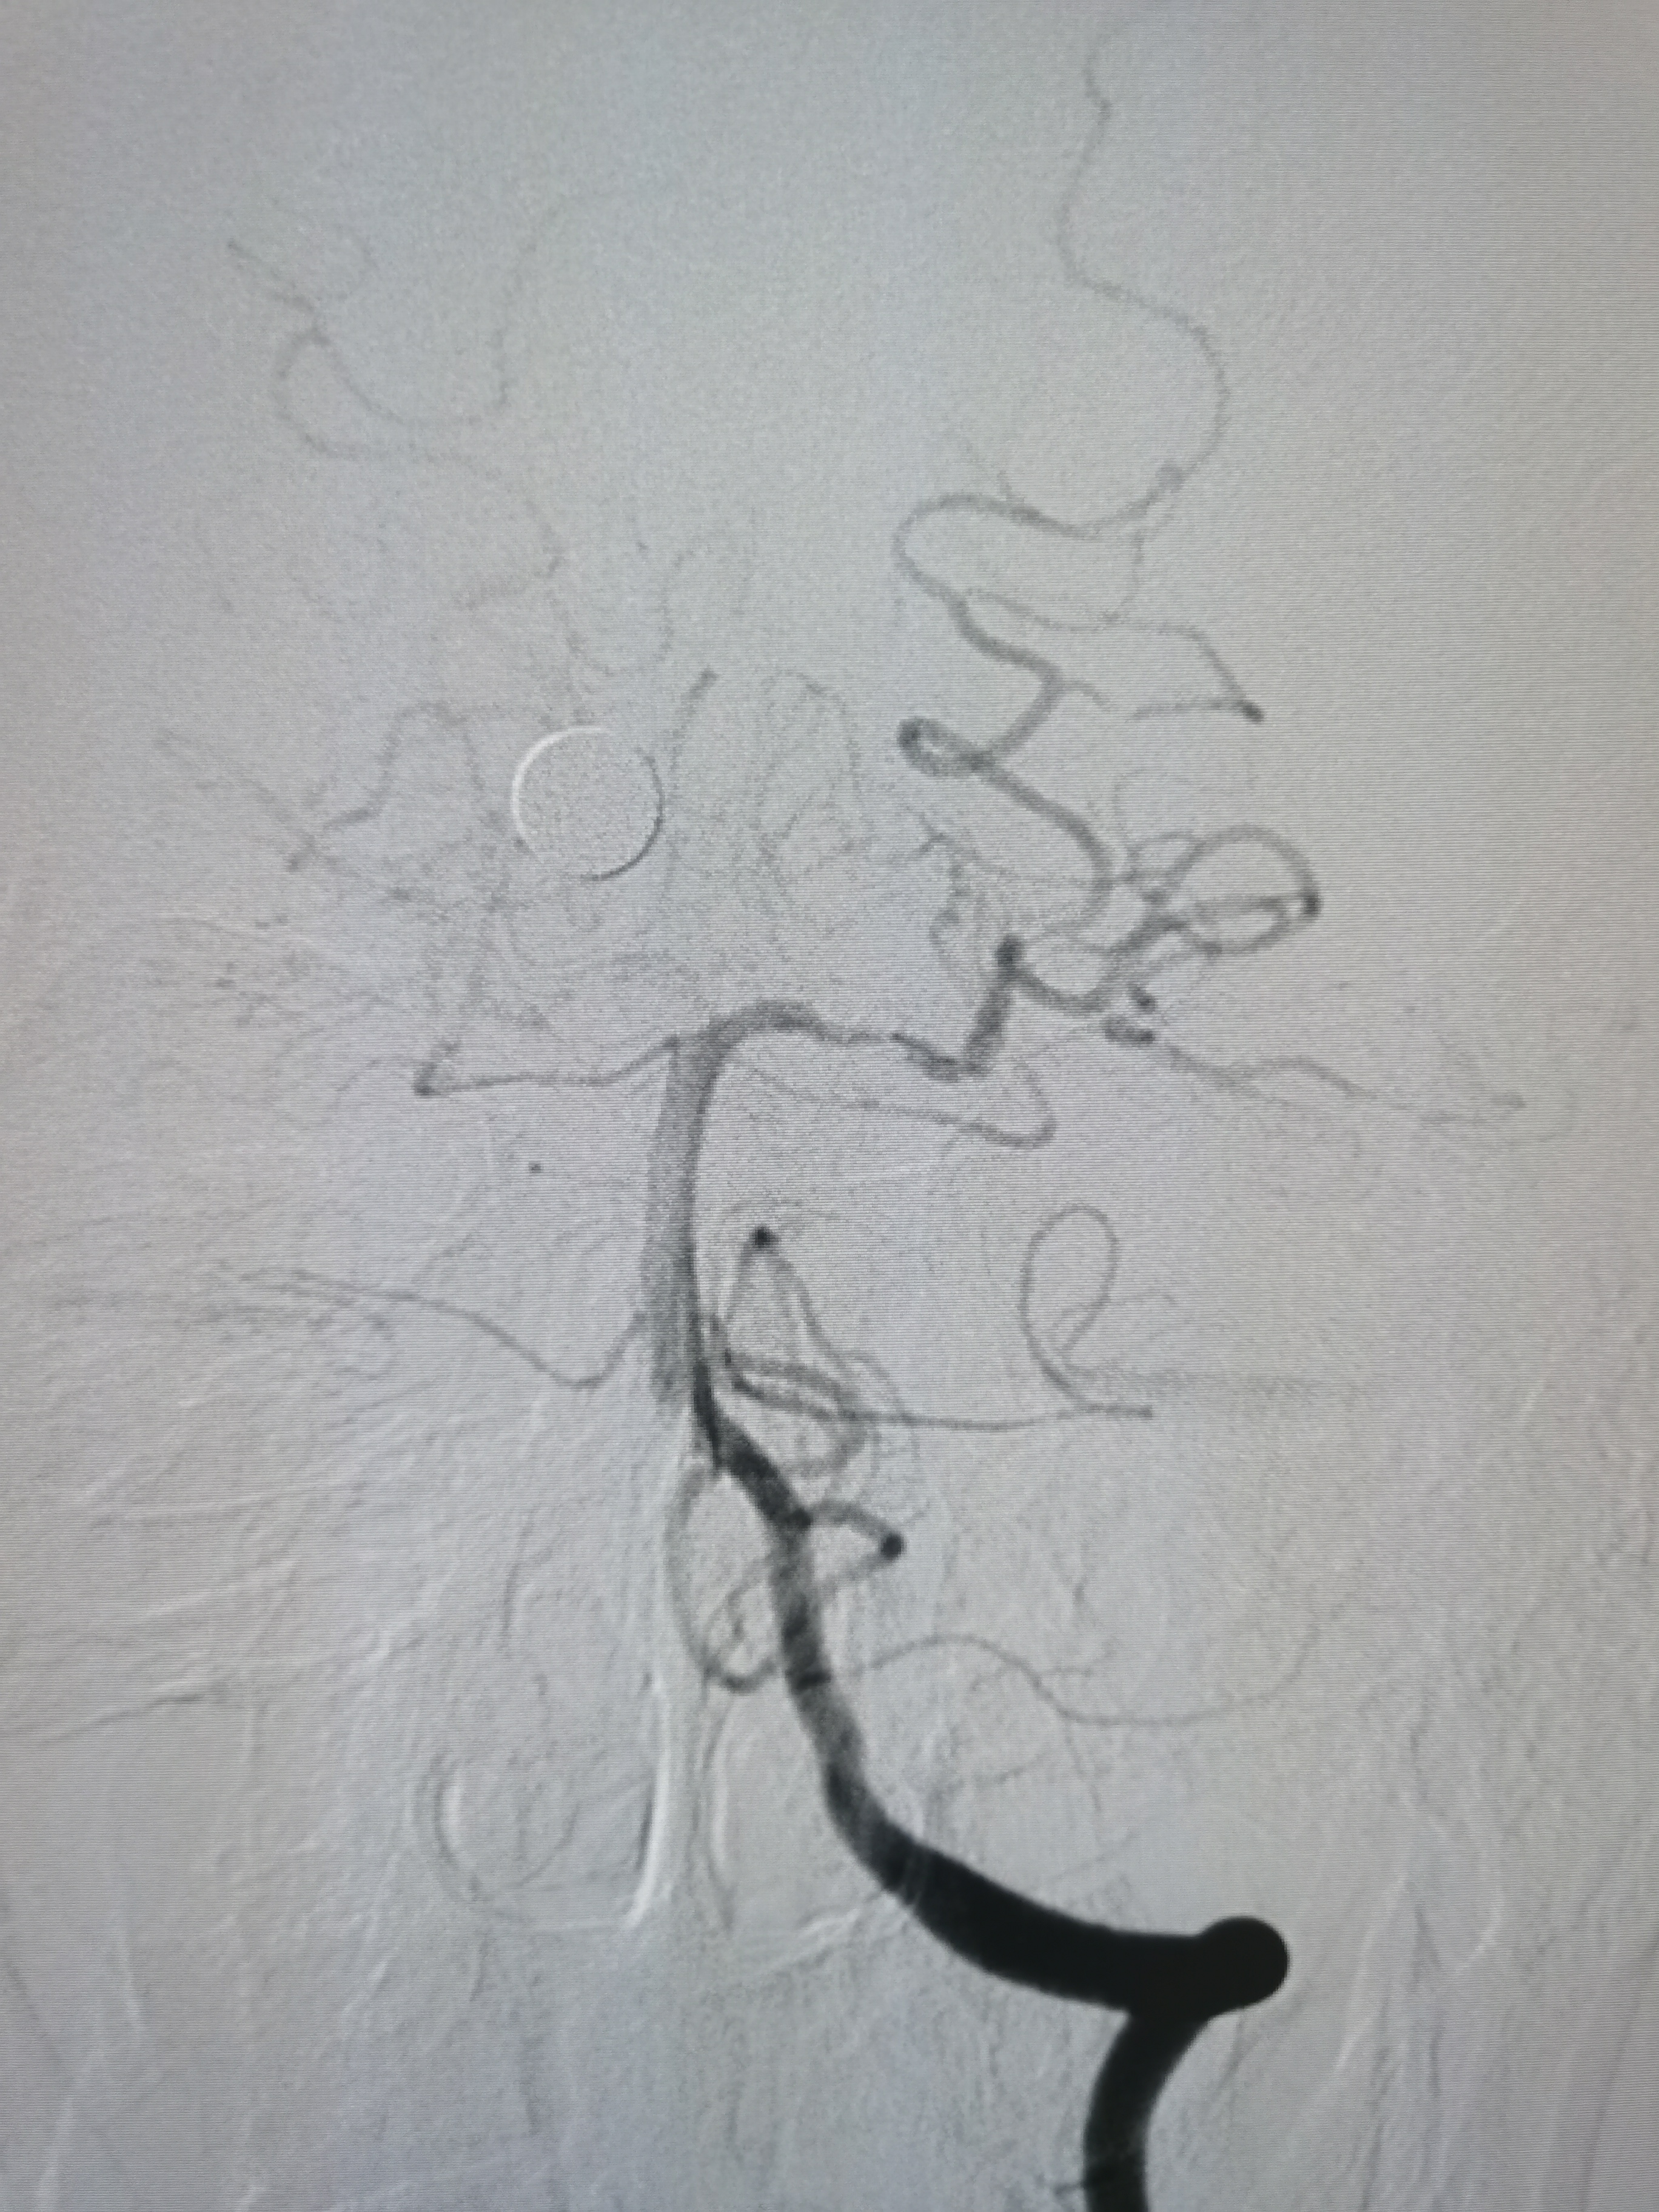

扩张后造影见血管再通,血流通畅。

侧位造影见血流通畅。

观察15分钟后造影血流通畅,未见夹层及明显弹性回缩。

复查造影见颅内狭窄解除,血流通畅,遂未再植入支架,撤出导丝及各级系统,结束手术。患者麻醉苏醒顺利,无新发神经系统症状,给予替罗非班持续泵入,监测生命体征,控制血压避免再灌注损伤。